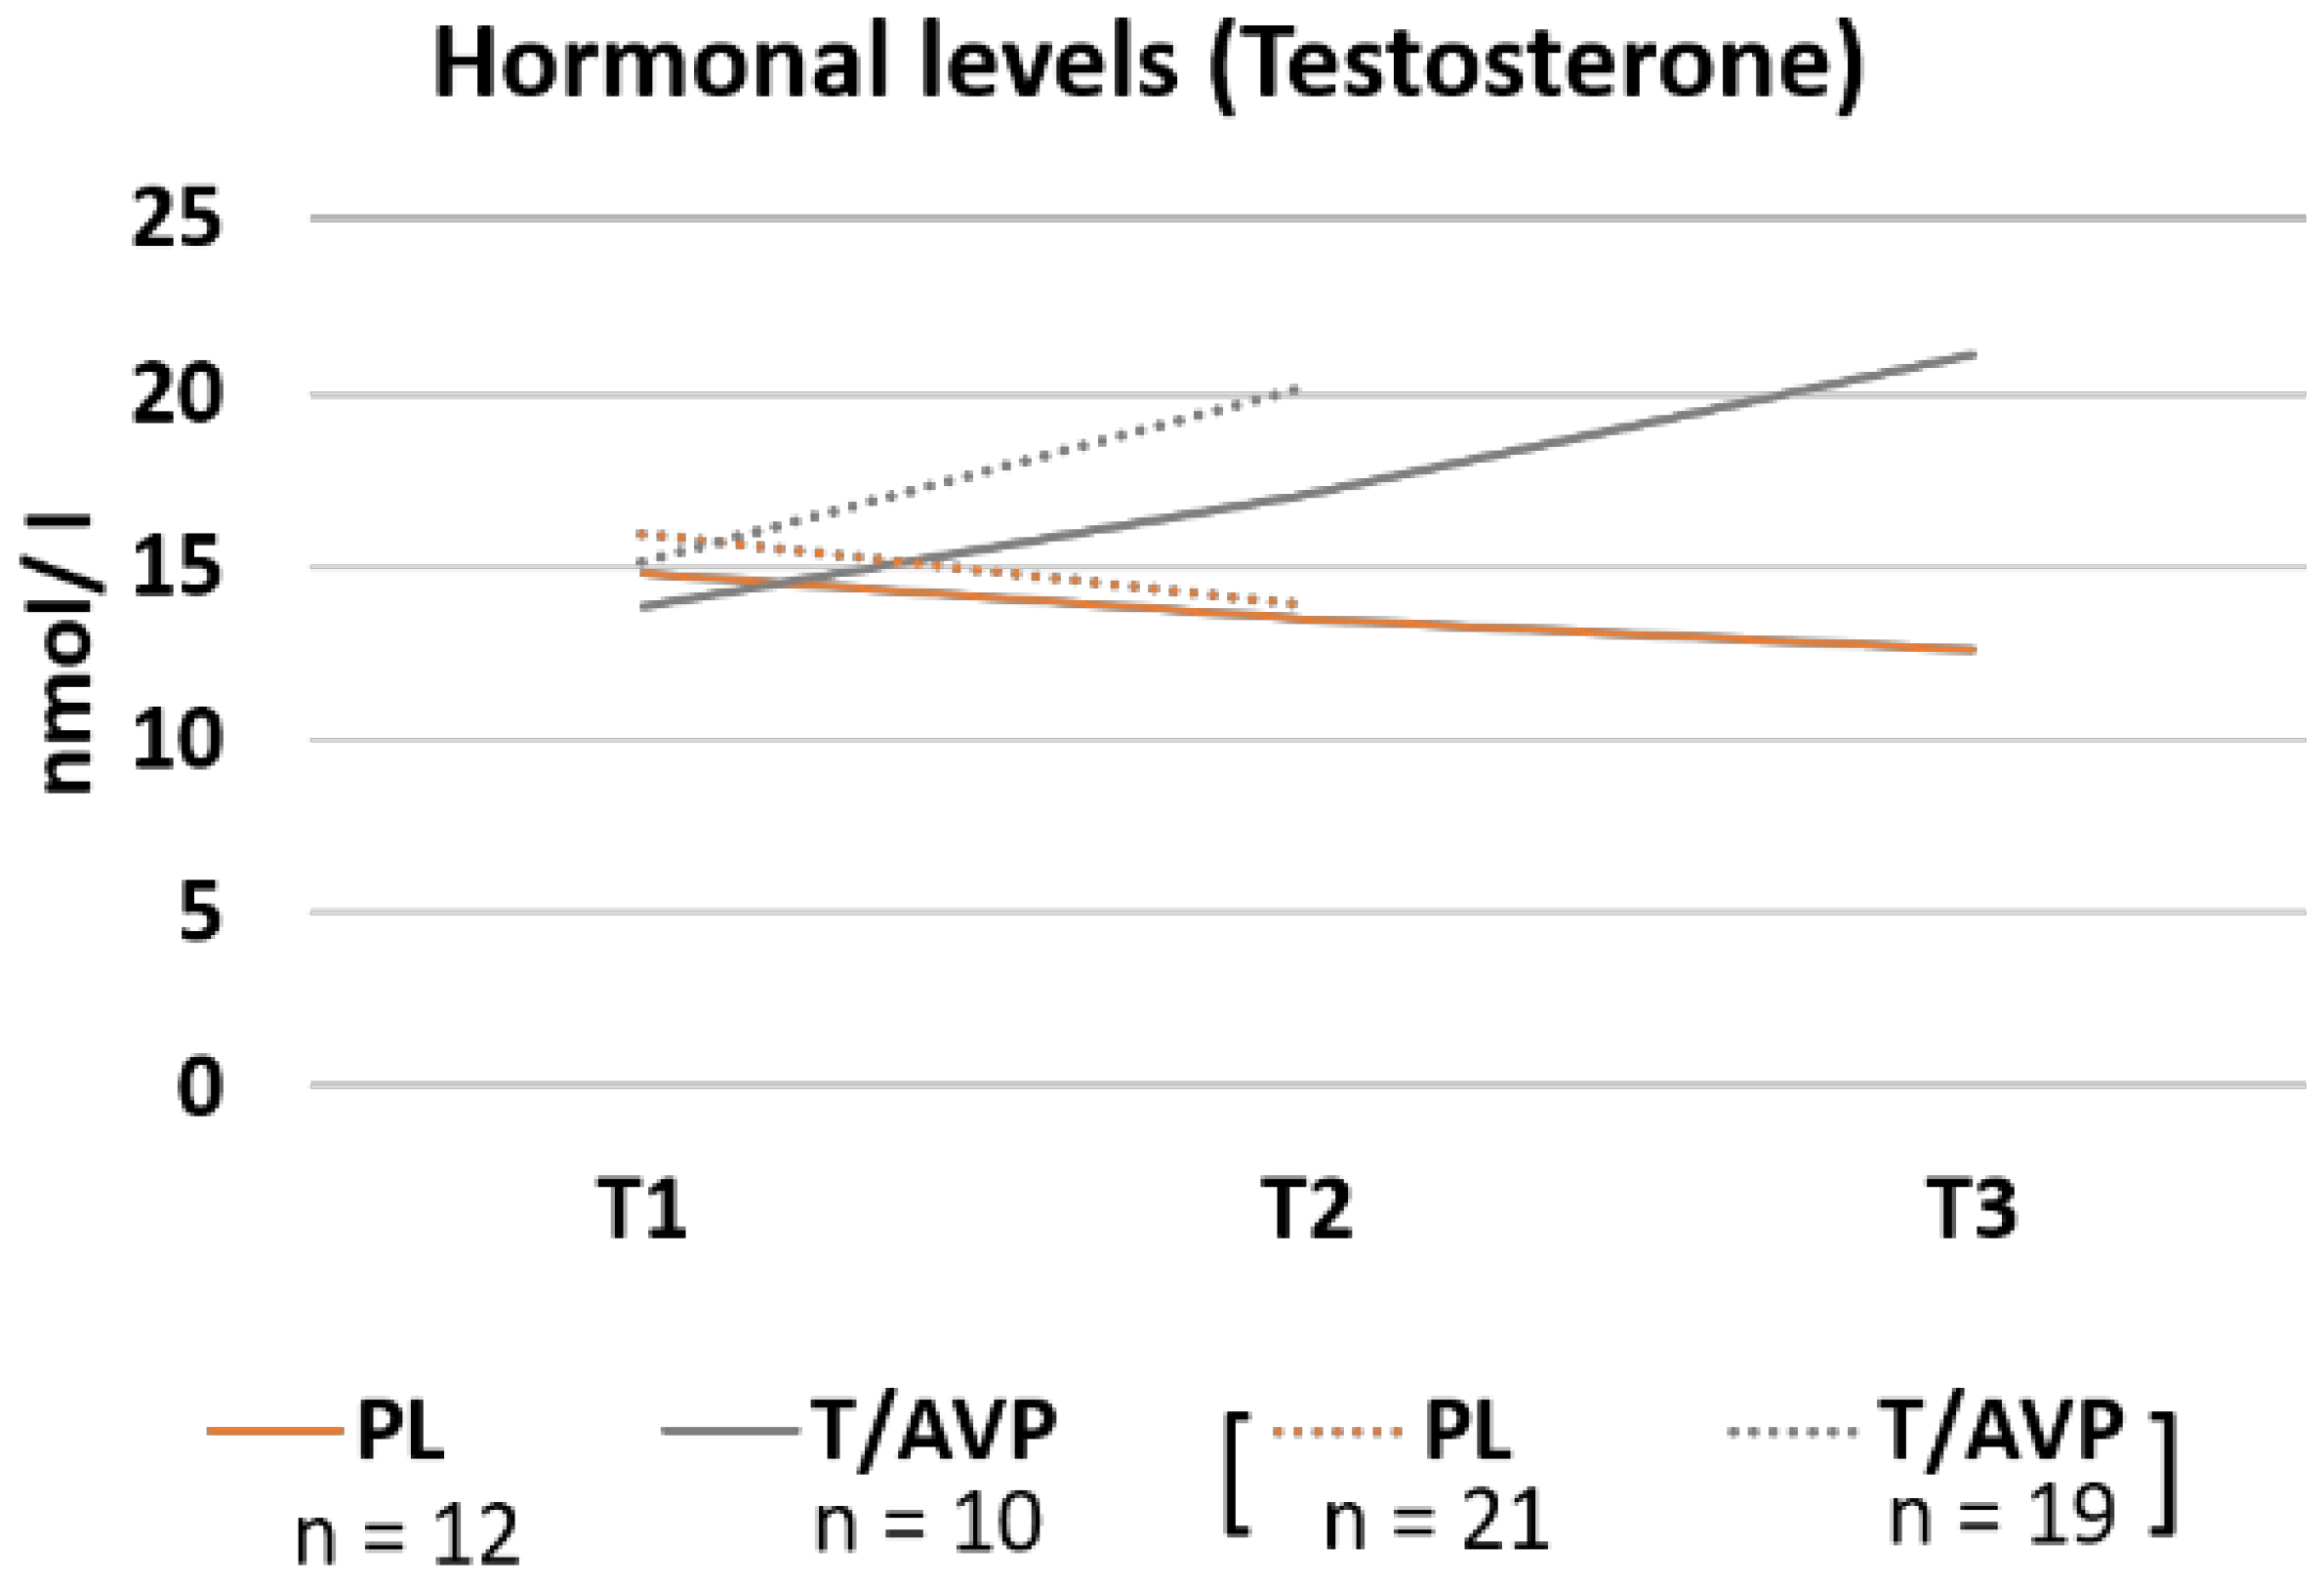

3.2. Hormone Concentration